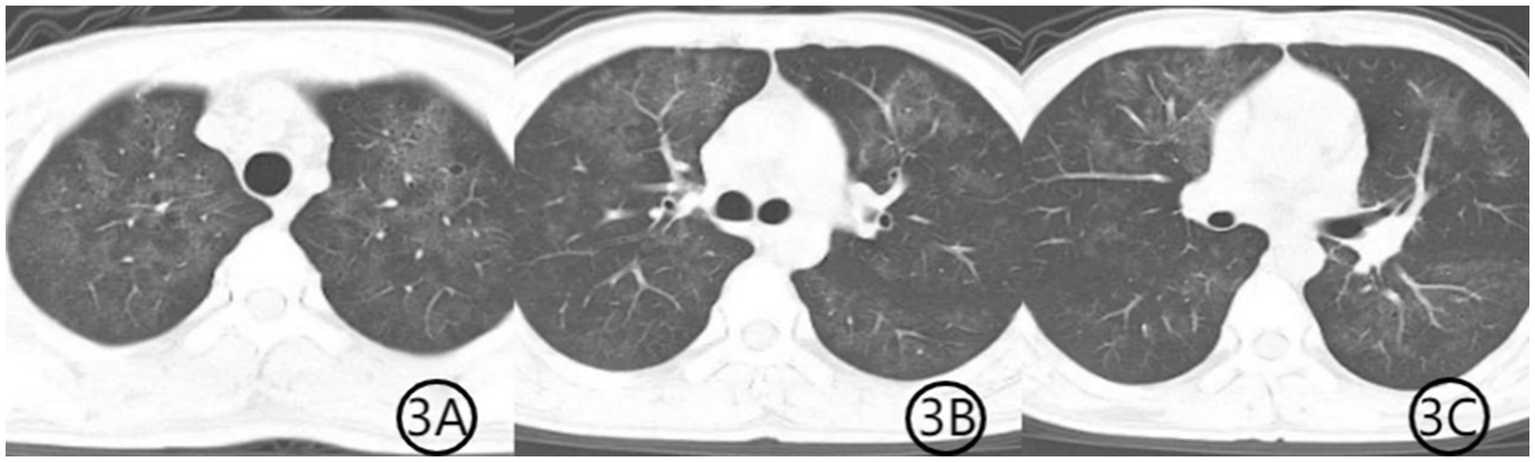

Figure 3

(A–C) Chest CT scan after 3 weeks of treatment. Axial CT images demonstrate further resolution of the previous pulmonary abnormalities. The patchy consolidation has markedly improved, the air bronchogram sign has disappeared, and the diffuse ground-glass opacities have significantly resolved, indicating substantial clinical and radiological recovery.